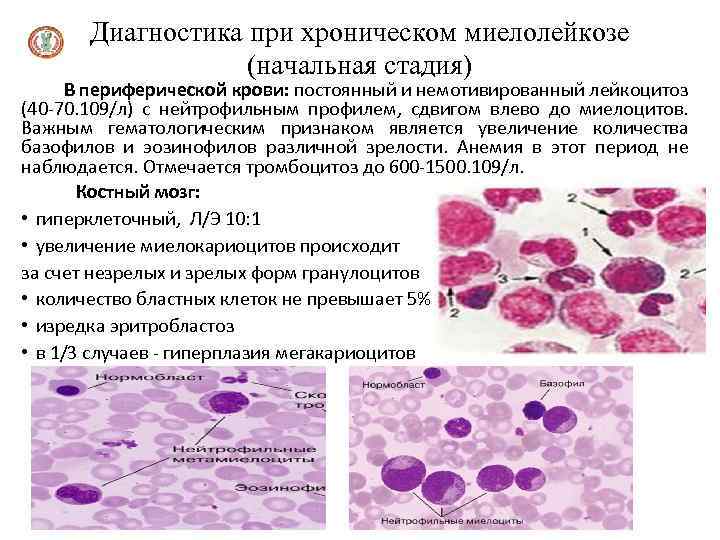

Диагностика при хроническом миелолейкозе (начальная стадия) В периферической крови: постоянный и немотивированный лейкоцитоз (40 -70. 109/л) с нейтрофильным профилем, сдвигом влево до миелоцитов. Важным гематологическим признаком является увеличение количества базофилов и эозинофилов различной зрелости. Анемия в этот период не наблюдается. Отмечается тромбоцитоз до 600 -1500. 109/л. Костный мозг: • гиперклеточный, Л/Э 10: 1 • увеличение миелокариоцитов происходит за счет незрелых и зрелых форм гранулоцитов • количество бластных клеток не превышает 5% • изредка эритробластоз • в 1/3 случаев - гиперплазия мегакариоцитов